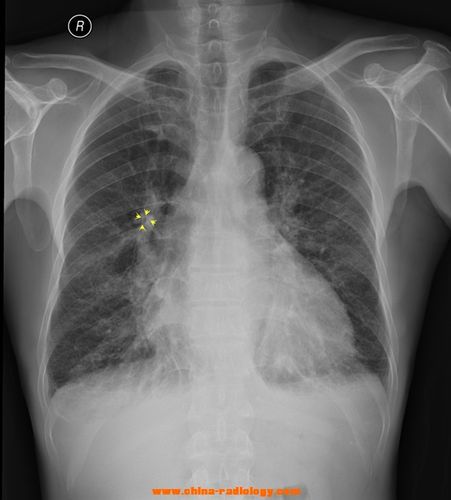

肺不张胸片典型图片

肺不张胸片典型图片,肺不张胸片表现图片

肺不张胸片表现图片

肺不张胸片表现

肺不张胸片

胸片正常图片结节影